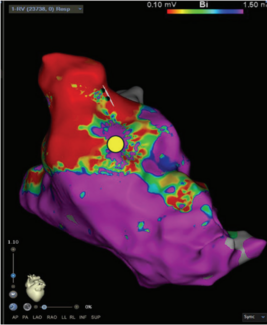

Ibragim Al-Seykal, MD; Tobias Ahnert; Ankit Maheshwari, MD

Ibragim Al-Seykal, MD, and colleagues describe a case of successful left ventricular summit premature ventricular complex ablation.